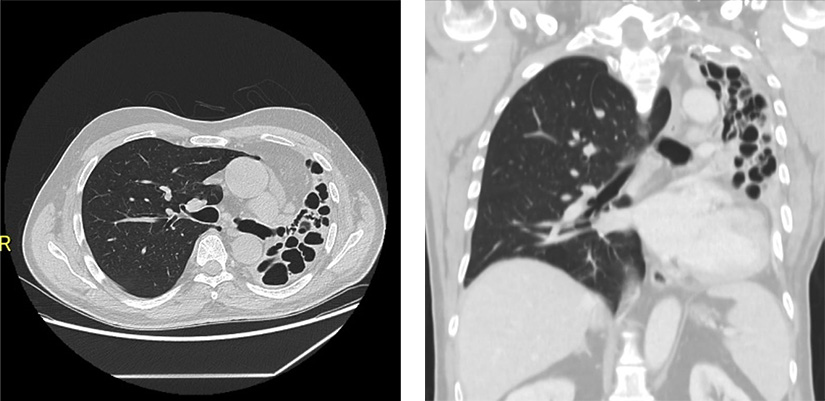

Examenul CT toracic arata distructia completa a plamanului restant stang prin bronsiectazii chistice mari de pana la 3 cm. Nu se evidentiaza deloc structura pulmonara normala.

„Severitatea acestui caz a fost notabila si a putut fi evidentiata la examenul CT toracic de inalta rezolutie care a evidentiat un plaman restant distrus in totalitate, complet ocupat de multiple bronsiectazii chistice, unele avand dimensiunea de peste 3 centimetri, care comunicau intre ele. La patrunderea in cavitatea pleurala s-a observat ca plamanul era aderent pe toate suprafetele.